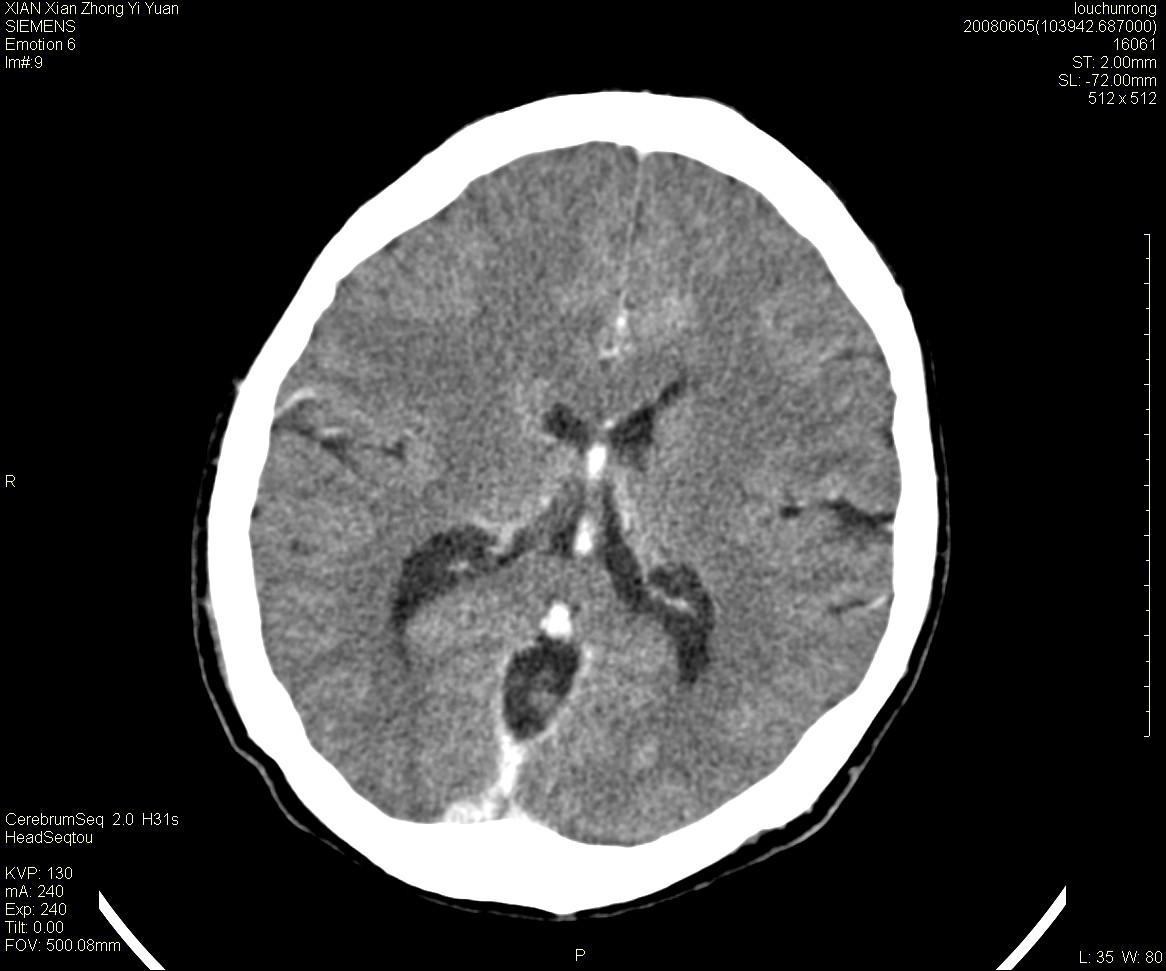

标题: CT13860:F52Y,,头外伤致头晕半天,以前无不适。 [打印本页]

标题: CT13860:F52Y,,头外伤致头晕半天,以前无不适。

层厚2mm。

左侧侧室内血管异常增粗,考虑血管变异或血管瘤可能,余未见异常

静脉窦血栓? mri检查

中线附近、枕叶近枕骨处及脑内多发点条状强化影,考虑血管异常?

大脑大静脉池内的密度不均,双侧脑室增宽,我看右异常这块。战友们看看